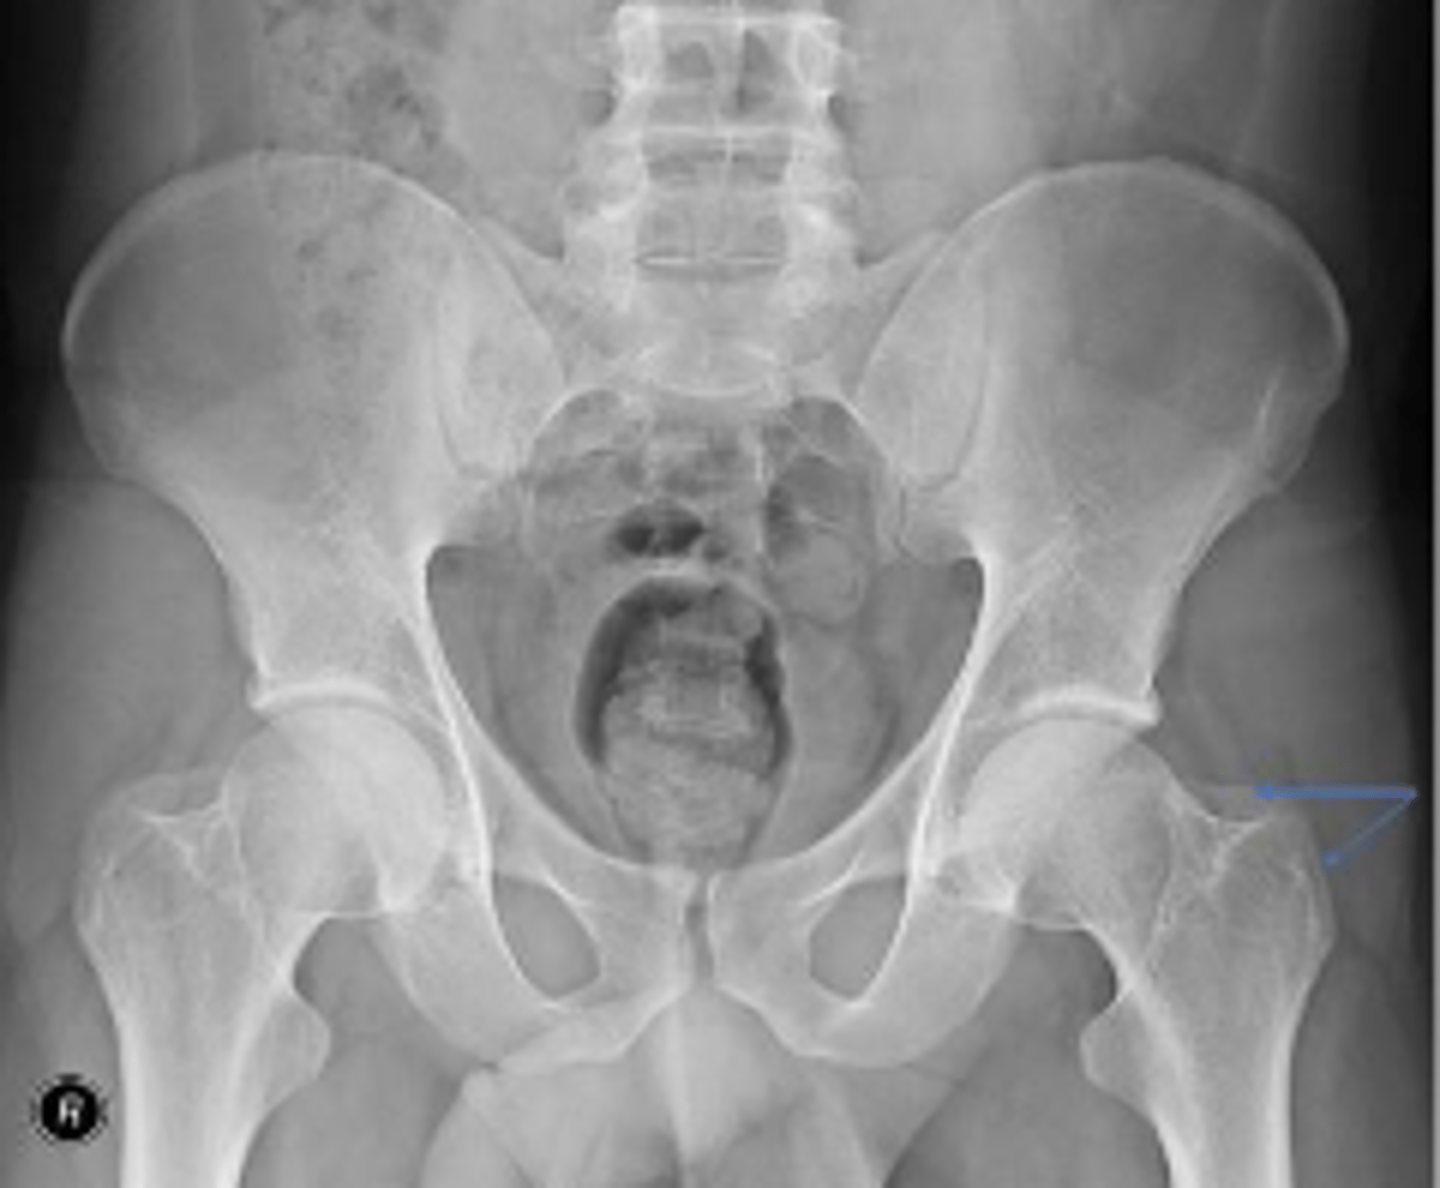

AP pelvis or bilateral hips

What is the name of the radiographic view?

10-15 degrees

How many degrees of internal rotation of the lower extremities is required for this view?

Iliac crest

What are the arrows pointing to?

Sacrum

What is the anatomical structure in between the lines?

ASIS

Left ischial spine

Sigmoid colon

What is outlined?

Right sacroiliac joint

What joint space are the arrows pointing to?

Pubic symphysis

What joint space is the arrow pointing to?

L4/L5 IVD space

Which IVD space is indicated by the arrows?

PSIS

Lesser trochanter of the left femur

Right L5 transverse process

Coccyx

Left obturator foramen

Left superior pubic ramus

Left inferior pubic ramus

AIIS

Soft tissue outline

Right ischial tuberosity

Proximal lateral cortical outline of the diaphysis of the right femur

Right pelvic teardrop

Phleboliths

Greater trochanter of the right femur

Right S3 superior border of the sacral foramen

Greater trochanter of the left femur

L3/L4 IVD space

What IVD space is indicated by the arrows?